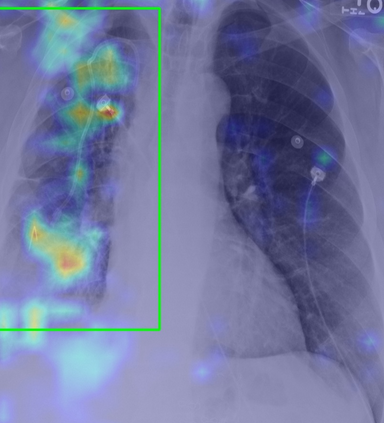

Tuberculosis remains a critical global health issue, particularly in resource-limited and remote areas. Early detection is vital for treatment, yet the lack of skilled radiologists underscores the need for artificial intelligence (AI)-driven screening tools. Developing reliable AI models is challenging due to the necessity for large, high-quality datasets, which are costly to obtain. To tackle this, we propose a teacher--student framework which enhances both disease and symptom detection on chest X-rays by integrating two supervised heads and a self-supervised head. Our model achieves an accuracy of 98.85% for distinguishing between COVID-19, tuberculosis, and normal cases, and a macro-F1 score of 90.09% for multilabel symptom detection, significantly outperforming baselines. The explainability assessments also show the model bases its predictions on relevant anatomical features, demonstrating promise for deployment in clinical screening and triage settings.